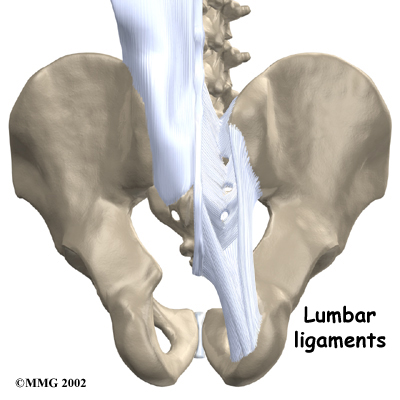

The lumbar spine is supported by ligaments and muscles. The ligaments, which connect bones together, are arranged in layers and run in multiple directions. connect the bones of the lumbar spine to the sacrum (the bone below L5) and pelvis.